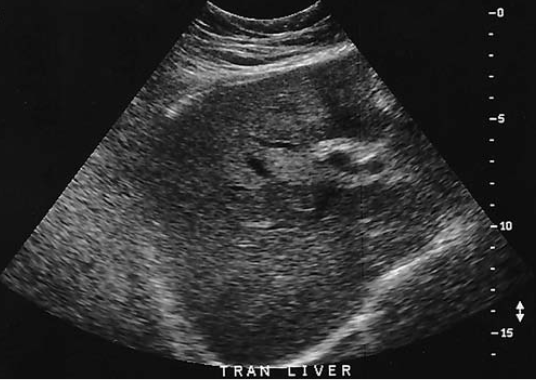

an obese patient presents with history of elevated liver function tests discovered during a life insurance medical exam. the patient has no complaints. Sono of this image is most sus for

fatty infiltration